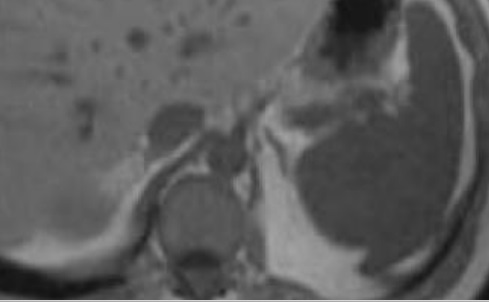

. Image

radiologique IRM d'une hemangiome da la rate

ponderee sur T2 FatSat . Aspect de masse hypersignal

, hetérogène de bien limité situé au milieu de la

rate . |